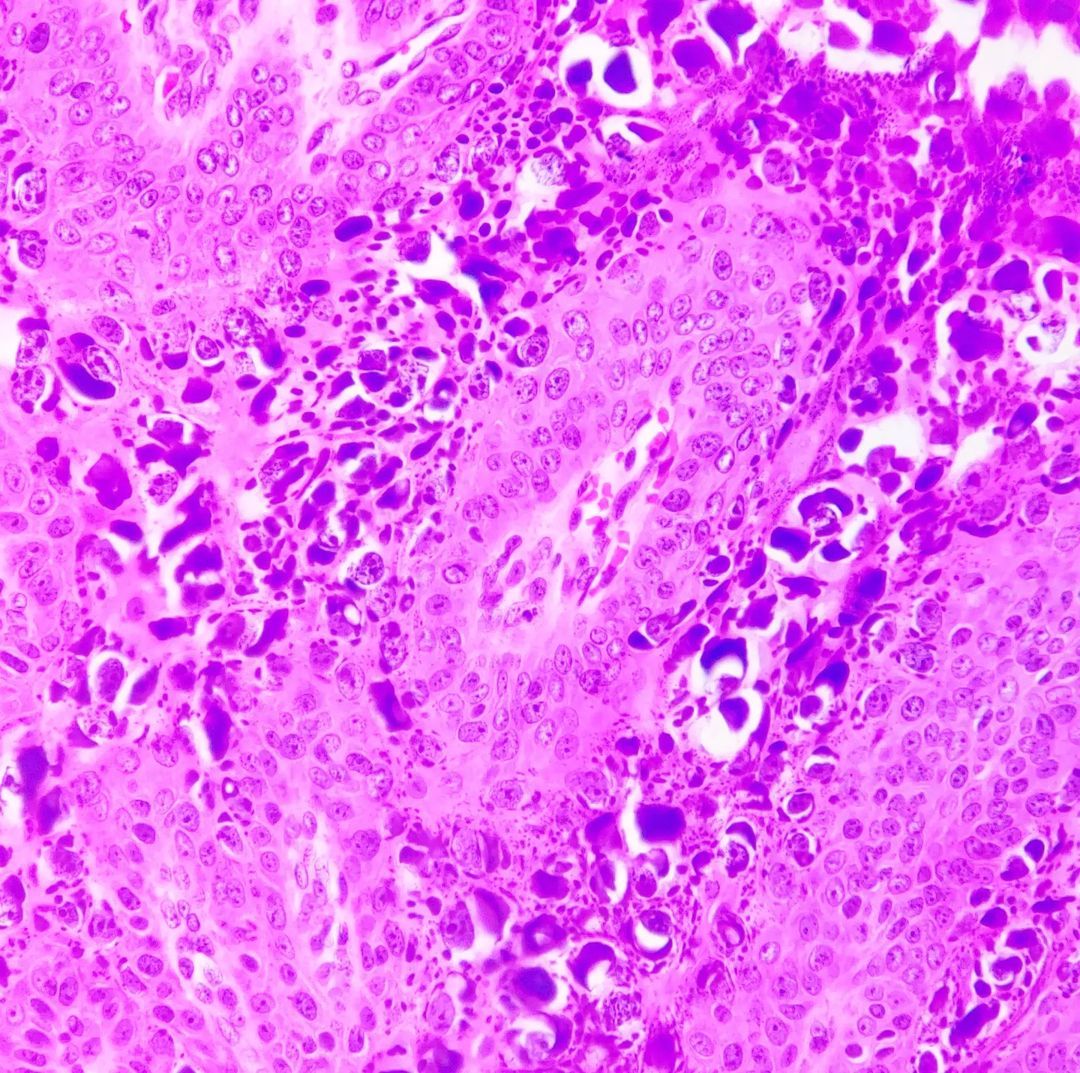

Microscopic (histologic) description

- Condyloma acuminatum (venereal / genital warts) (Head Neck Pathol 2019;13:80):

- More massive acanthosis with bulbous rete ridges (condyloma means fist or knuckle)

- Koilocytes in the upper spinous layer

- Parakeratosis ofen in the valleys of the epithelium (crypt parakeratosis) (see condyloma)

Microscopic (histologic) images

Contributed by Heba Ahmed Abdelkader, M.D., Hillary Rose Elwood, M.D., AFIP,

@MirunaPopescu13 on Twitter and @shilpa_rakesh_path on Instagram